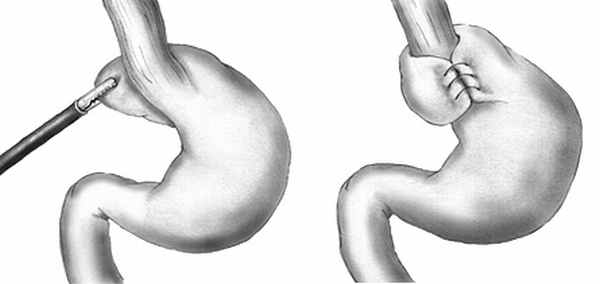

Фундопликация по Ниссену

Фундопликация по Ниссену (англ. Nissen fundoplication) — антирефлюксная операция, заключающаяся в том, что дно желудка обворачивают вокруг пищевода, создавая манжетку, препятствующая забросу желудочного содержимого в пищевод. Впервые антирефлюксная операция — фундопликация была проведена Рудольфом Ниссеном 1955 году, предложившим формировать муфту из верхней части дна желудка состоявшую в 360-градусной пликации 5-сантиметровой манжетки вокруг нижней части пищевода (Васнёв О.С.). При проведении фундопликации восстанавливается не только анатомическое строение, но и функциональное состояние нижнего пищеводного сфинктера: восстанавливается тонус, уменьшается количество преходящих расслаблений при растяжении желудка, улучшается его опорожнение.

Рис.1. Общая схема фундопликации по Ниссену

Фундопликация по Ниссену может выполняться как лапароскопически, так и открытым способом. Фундопликация по Ниссену, включая её модификации и в настоящее время считается «золотым стандартом» антирефлюксной хирургии.